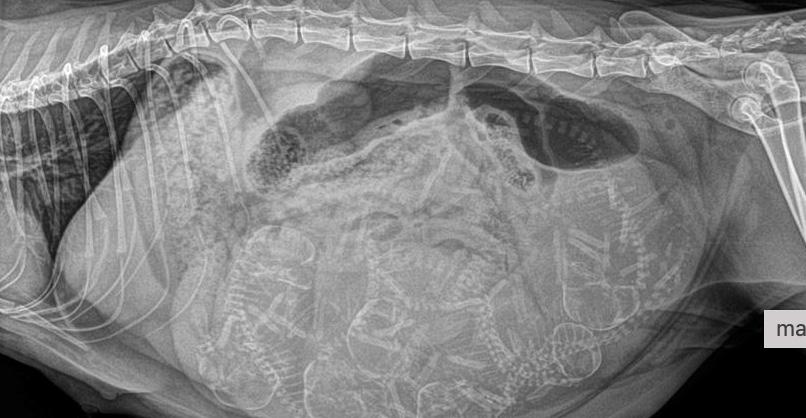

Did you know we can do pregnancy x-rays on late pregnant cats and dogs? From 7 weeks gestation onwards, this can help give an idea of how many puppies or kittens will be expected at the time of birth.

This adorable Mum Reign had a belly full of kittens, can you count how many from the radiograph taken?!

If you guessed 7, then you're right! Mum is loving her babies and we can't wait to watch them grow!